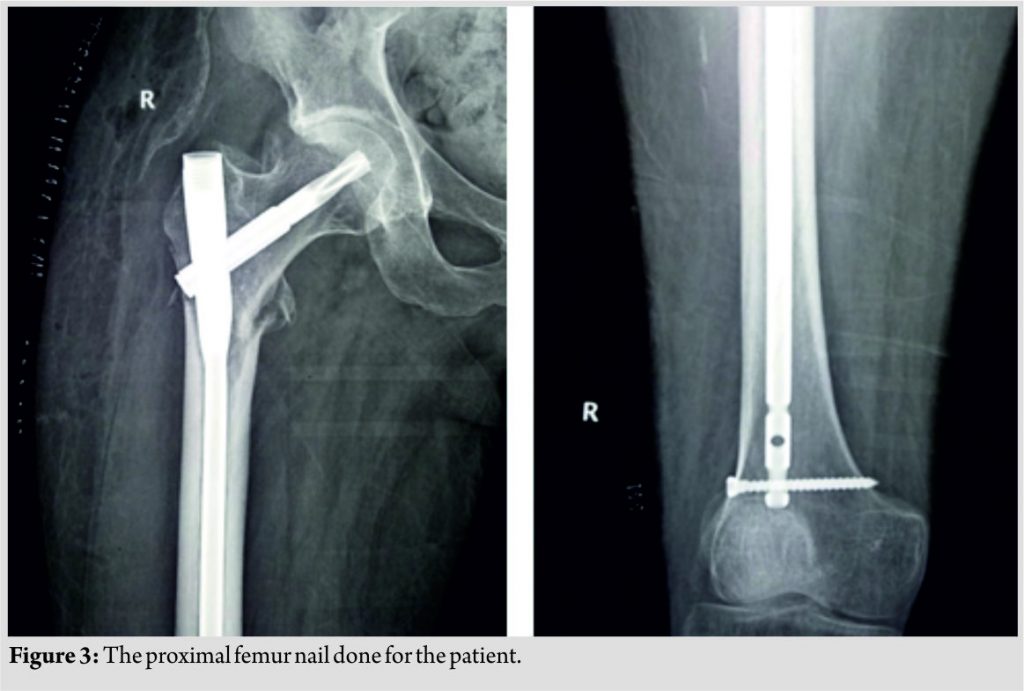

There was no improvement in the neurological status in the post-operative period, and the patient was on regular physiotherapy and rehabilitation. Plain radiology showed a fracture of the right subtrochanteric femur (Fig. 2). The patient biochemical profile was evaluated, which showed normal Vitamin D3 (23.79 ng/ml) and parathyroid hormone (PTH) levels (33.25 pg/ml). The dual-energy X-ray absorptiometry (DEXA) scan revealed osteopenia of the proximal femur (T score = −1.5). The patient was operated and closed proximal femur nailing was done to fix the fracture (Fig. 3). The patient had no intraoperative or post-operative complications. Early ROM exercises were initiated along with wheel chair mobilization. The patient was started on subcutaneous teriparatide with calcium and Vitamin D supplementation. At the last follow-up, he had supple joints and was kept under a home-based rehabilitation program.